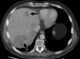

Cushing's syndrome is the collection of signs and symptoms due to prolonged exposure to glucocorticoids such as cortisol. Signs and symptoms may include high blood pressure, abdominal obesity but with thin arms and legs, reddish stretch marks, a round red face, a fat lump between the shoulders, weak muscles, weak bones, acne, and fragile skin that heals poorly. [Source: Wikipedia ]

Cushing syndrome